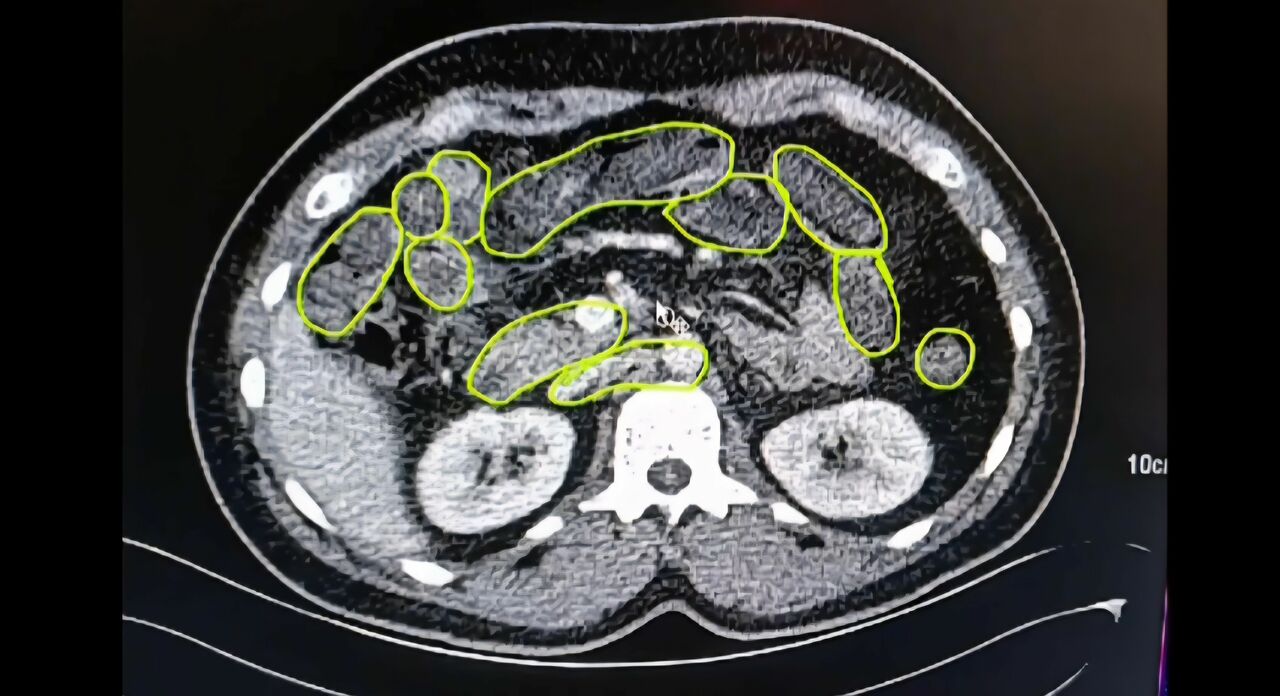

Araçta ve üzerlerinde yapılan aramalarda 20 gram uyuşturucu madde ile 117 adet uyuşturucu hap ele geçirildi. Şüpheliler, iç beden kontrolü için Kayseri Şehir Hastanesi’ne sevk edildi. Yapılan muayenelerde, mide ve bağırsaklarında kapsül şeklinde çok sayıda yabancı madde tespit edildi.